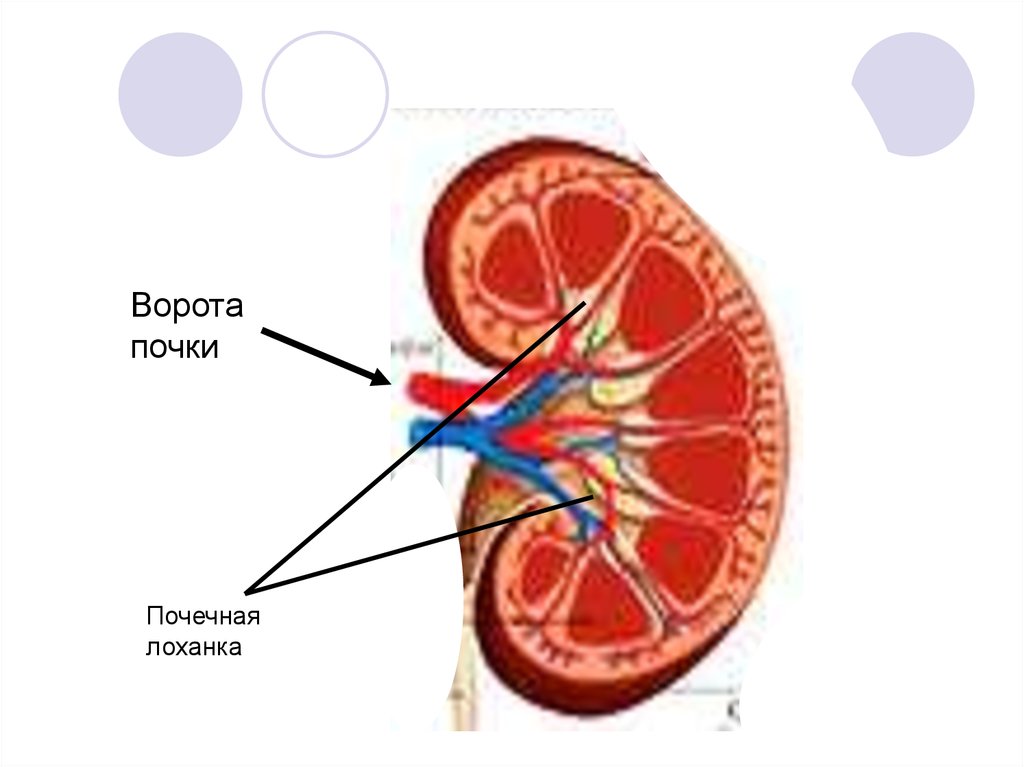

Интраренальная лоханка: рентгеновские снимки и примеры